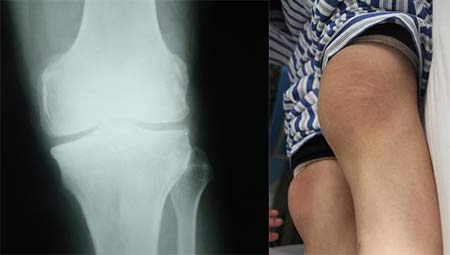

(图:陈先生膝关节X线片显示关节肿大,关节间隙变窄)

X线示:多处软骨组织破坏,关节畸形明显狭窄。